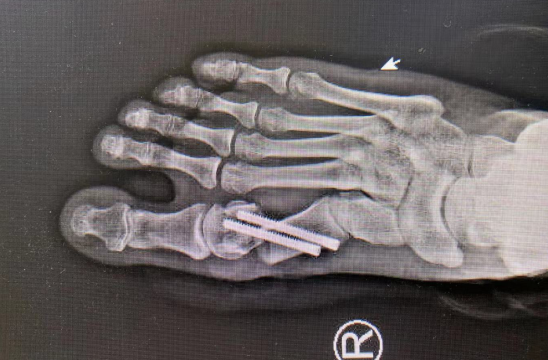

很快,曹广超主任胡帆医生手术小组给患者进行了右足微创踇外翻手术,麻醉师采用超声引导下神经阻滞,手术医生通过不到一厘米切口,切除增生的踇囊,利用4毫米进口超声磨锯微创截断跖骨,完美修整踇外翻。